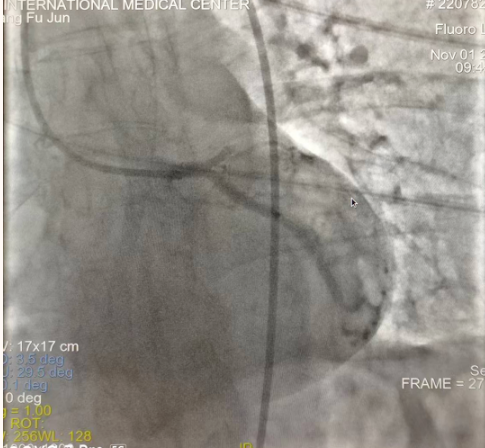

閉塞的血管再通時(shí)間取決于急救時(shí)長、轉(zhuǎn)運(yùn)時(shí)長和治療時(shí)長,在前兩方面,醫(yī)院已為患者爭取了最短時(shí)間?;颊呒覍龠h(yuǎn)在陜北,雖然已在趕來的路上,但最快抵達(dá)西安也要3小時(shí),在與患者家屬電話溝通同意急診手術(shù)后,醫(yī)療總值班代家屬簽字,康曉軍在請示心臟病醫(yī)院王海昌院長及心臟內(nèi)科CCU尚福軍主任后,積極進(jìn)行術(shù)前準(zhǔn)備。在沒有家屬陪同、沒有交費(fèi)、沒有辦入院手續(xù)的情況下,患者經(jīng)胸痛中心綠色通道被送往心臟冠脈介入手術(shù)室,打通了完全閉塞的心臟前降支近段血管。